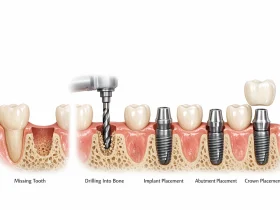

ایمپلنت دندان ناموفق چیست؟

ایمپلنت دندان زمانی ناموفق یا شکستخورده در نظر گرفته میشود که:

- ایمپلنت نتواند بهدرستی با استخوان فک جوش بخورد (Osseointegration)

- تحلیل استخوان اطراف ایمپلنت رخ دهد

- ایمپلنت لق، تکانخورده یا جدا شود

- عفونت شدید اطراف ایمپلنت وجود داشته باشد

- عدم ثبات اولیه پس از کاشت دیده شود

در اصطلاح علمی، وقتی استانداردهای موفقیت برآورده نشود (مثلاً حرکت ایمپلنت یا کاهش بیش از حد استخوان اطراف)، درمان بهعنوان شکست تلقی میشود.

۱. عدم جوش خوردن ایمپلنت با استخوان

ایمپلنت باید با استخوان فک جوش بخورد تا ثابت بماند. اگر این اتصال برقرار نشود، ایمپلنت بهدرستی در جای خود قرار نمیگیرد.